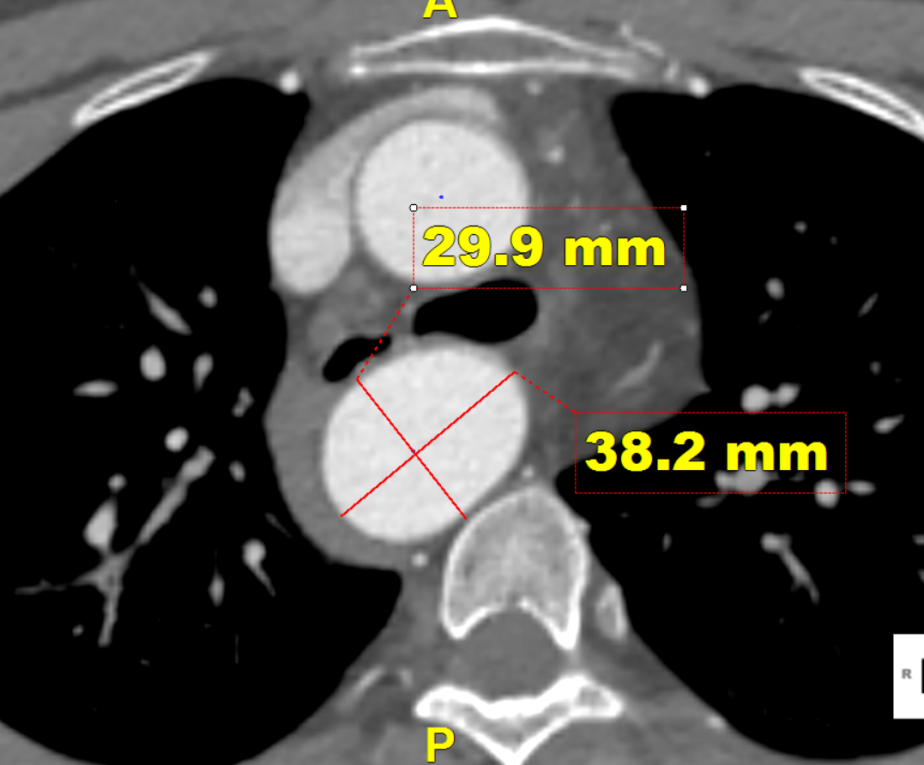

术前CTA提示右弓右降、合并Kommerell憩室,弓上各分支镜像分布。测量如下:

右弓右降,弓型陡峭,角度在40°左右

Kommerell憩室,38mm*30mm

考虑患者意愿,最后选择腔内手术方案。因该患者弓型陡峭,小弯侧锚定区较短,仅4.6mm,因此选择34mm直径、长度150mm支架,并考虑: